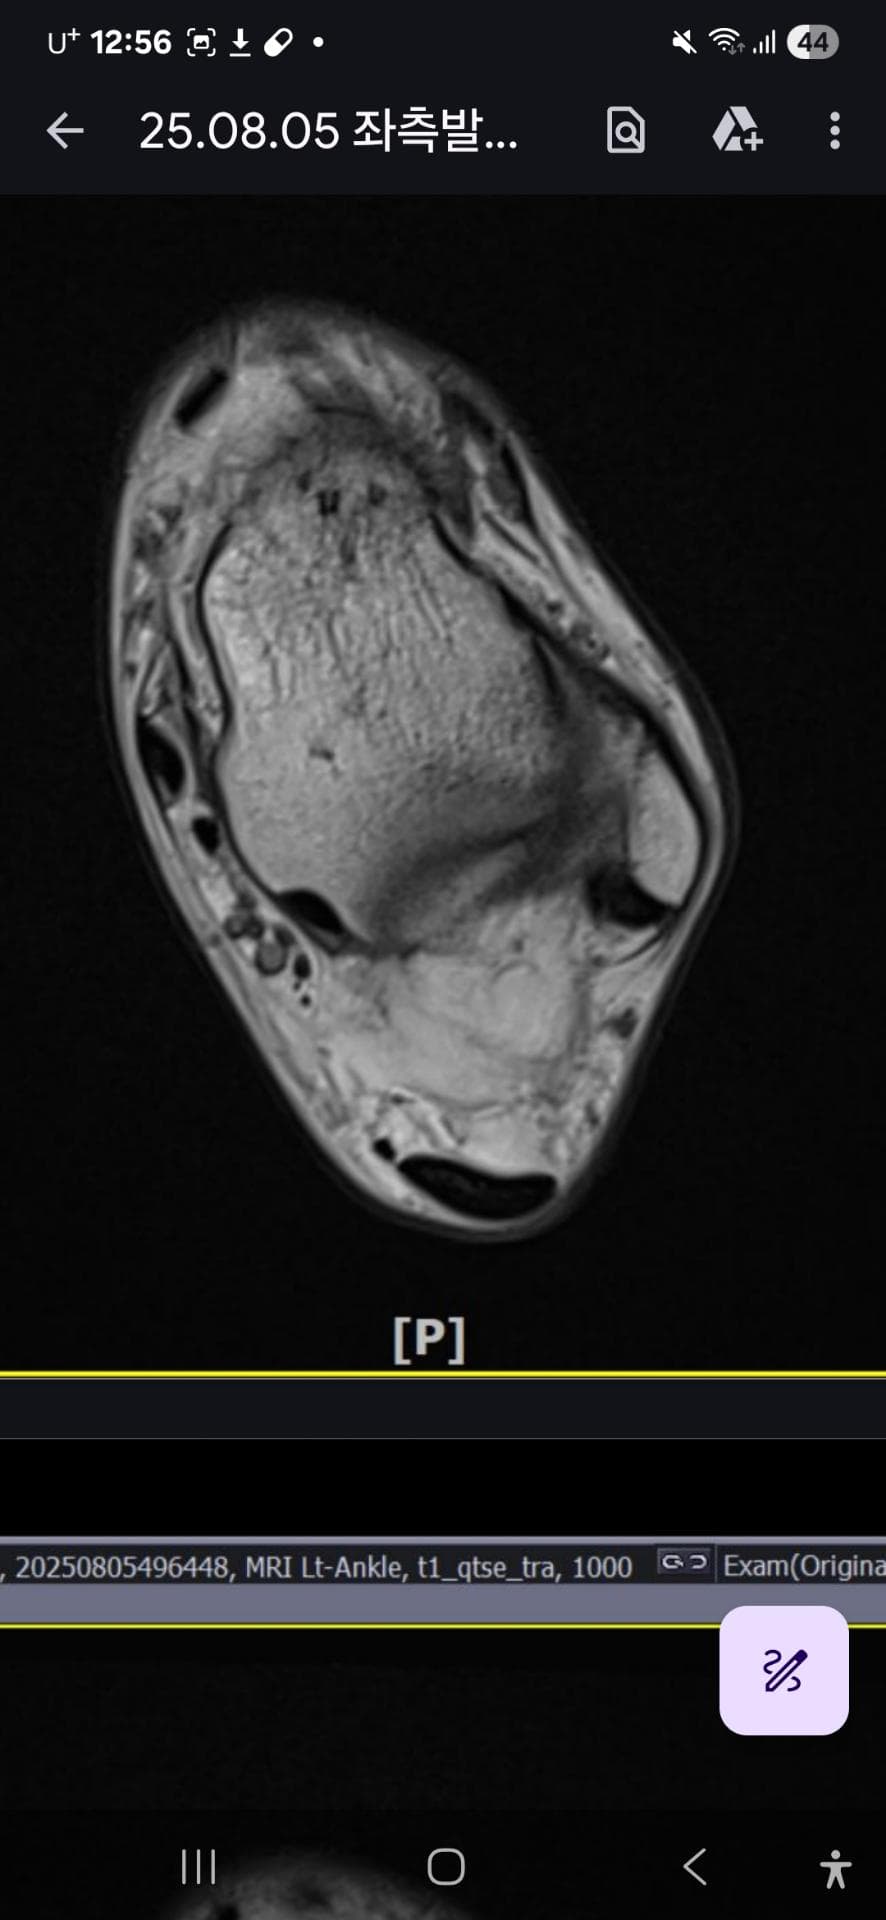

그래도 통증이 남아 8월 5일에 MRI를 촬영했는데, 병원에서는 “인대는 이어져 있고, 이 정도면 재활운동으로 호전될 것”이라는 설명을 들었습니다.

MRI 상 전거비인대와 발목 상태가 정말 회복 단계인지, 아니면 만성으로 넘어가는 건 아닌지 전문가분들의

의견을 듣고 싶습니다.

올려주신 mri를 보면 전거비인대는 연속성이 유지되고 있고 파열이나 큰 손상 흔적은 없어 재활로 회복 가능한 상태로 보입니다 다만 3개월 가까이 활동 시 통증과 미열감이 남아 있는 것은 조직 회복이 아직 완전히 끝나지 않았거나 주변 연부조직 관절 움직임 제한 등으로 인한 과민 반응일 수 있습니다.

초음파와 비교하면 mri 상으로 인대 연속성이 확인되므로 심각한 악화나 재파열은 아닌 것으로 판단됩니다